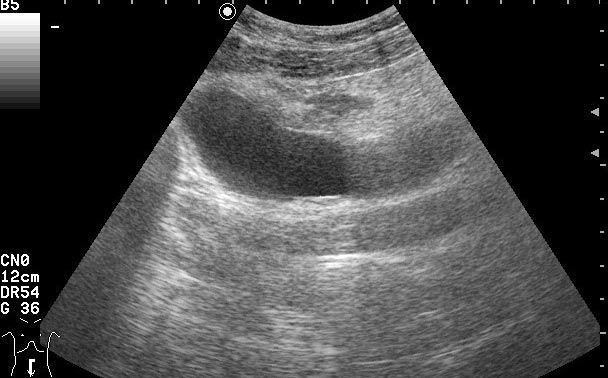

Пациентке была выполнена биопсия образования, назначена антибактериальная и противовоспалительная терапия.

Клиническое выздоровление через 2 недели. Сонограммы мочевого пузыря через 6 недель:

Если бы это было воспаление кисты, то мы бы видели изначально кисту с акустически непрозрачным содержимым. После лечения мы бы видели кисту с анэхогенным содержимым.zubr писал(а):У Митькова аналогичное образование названо воспаление кисты урахуса,что в принципе суть не меняет,а предполагает аналогичную тактику.